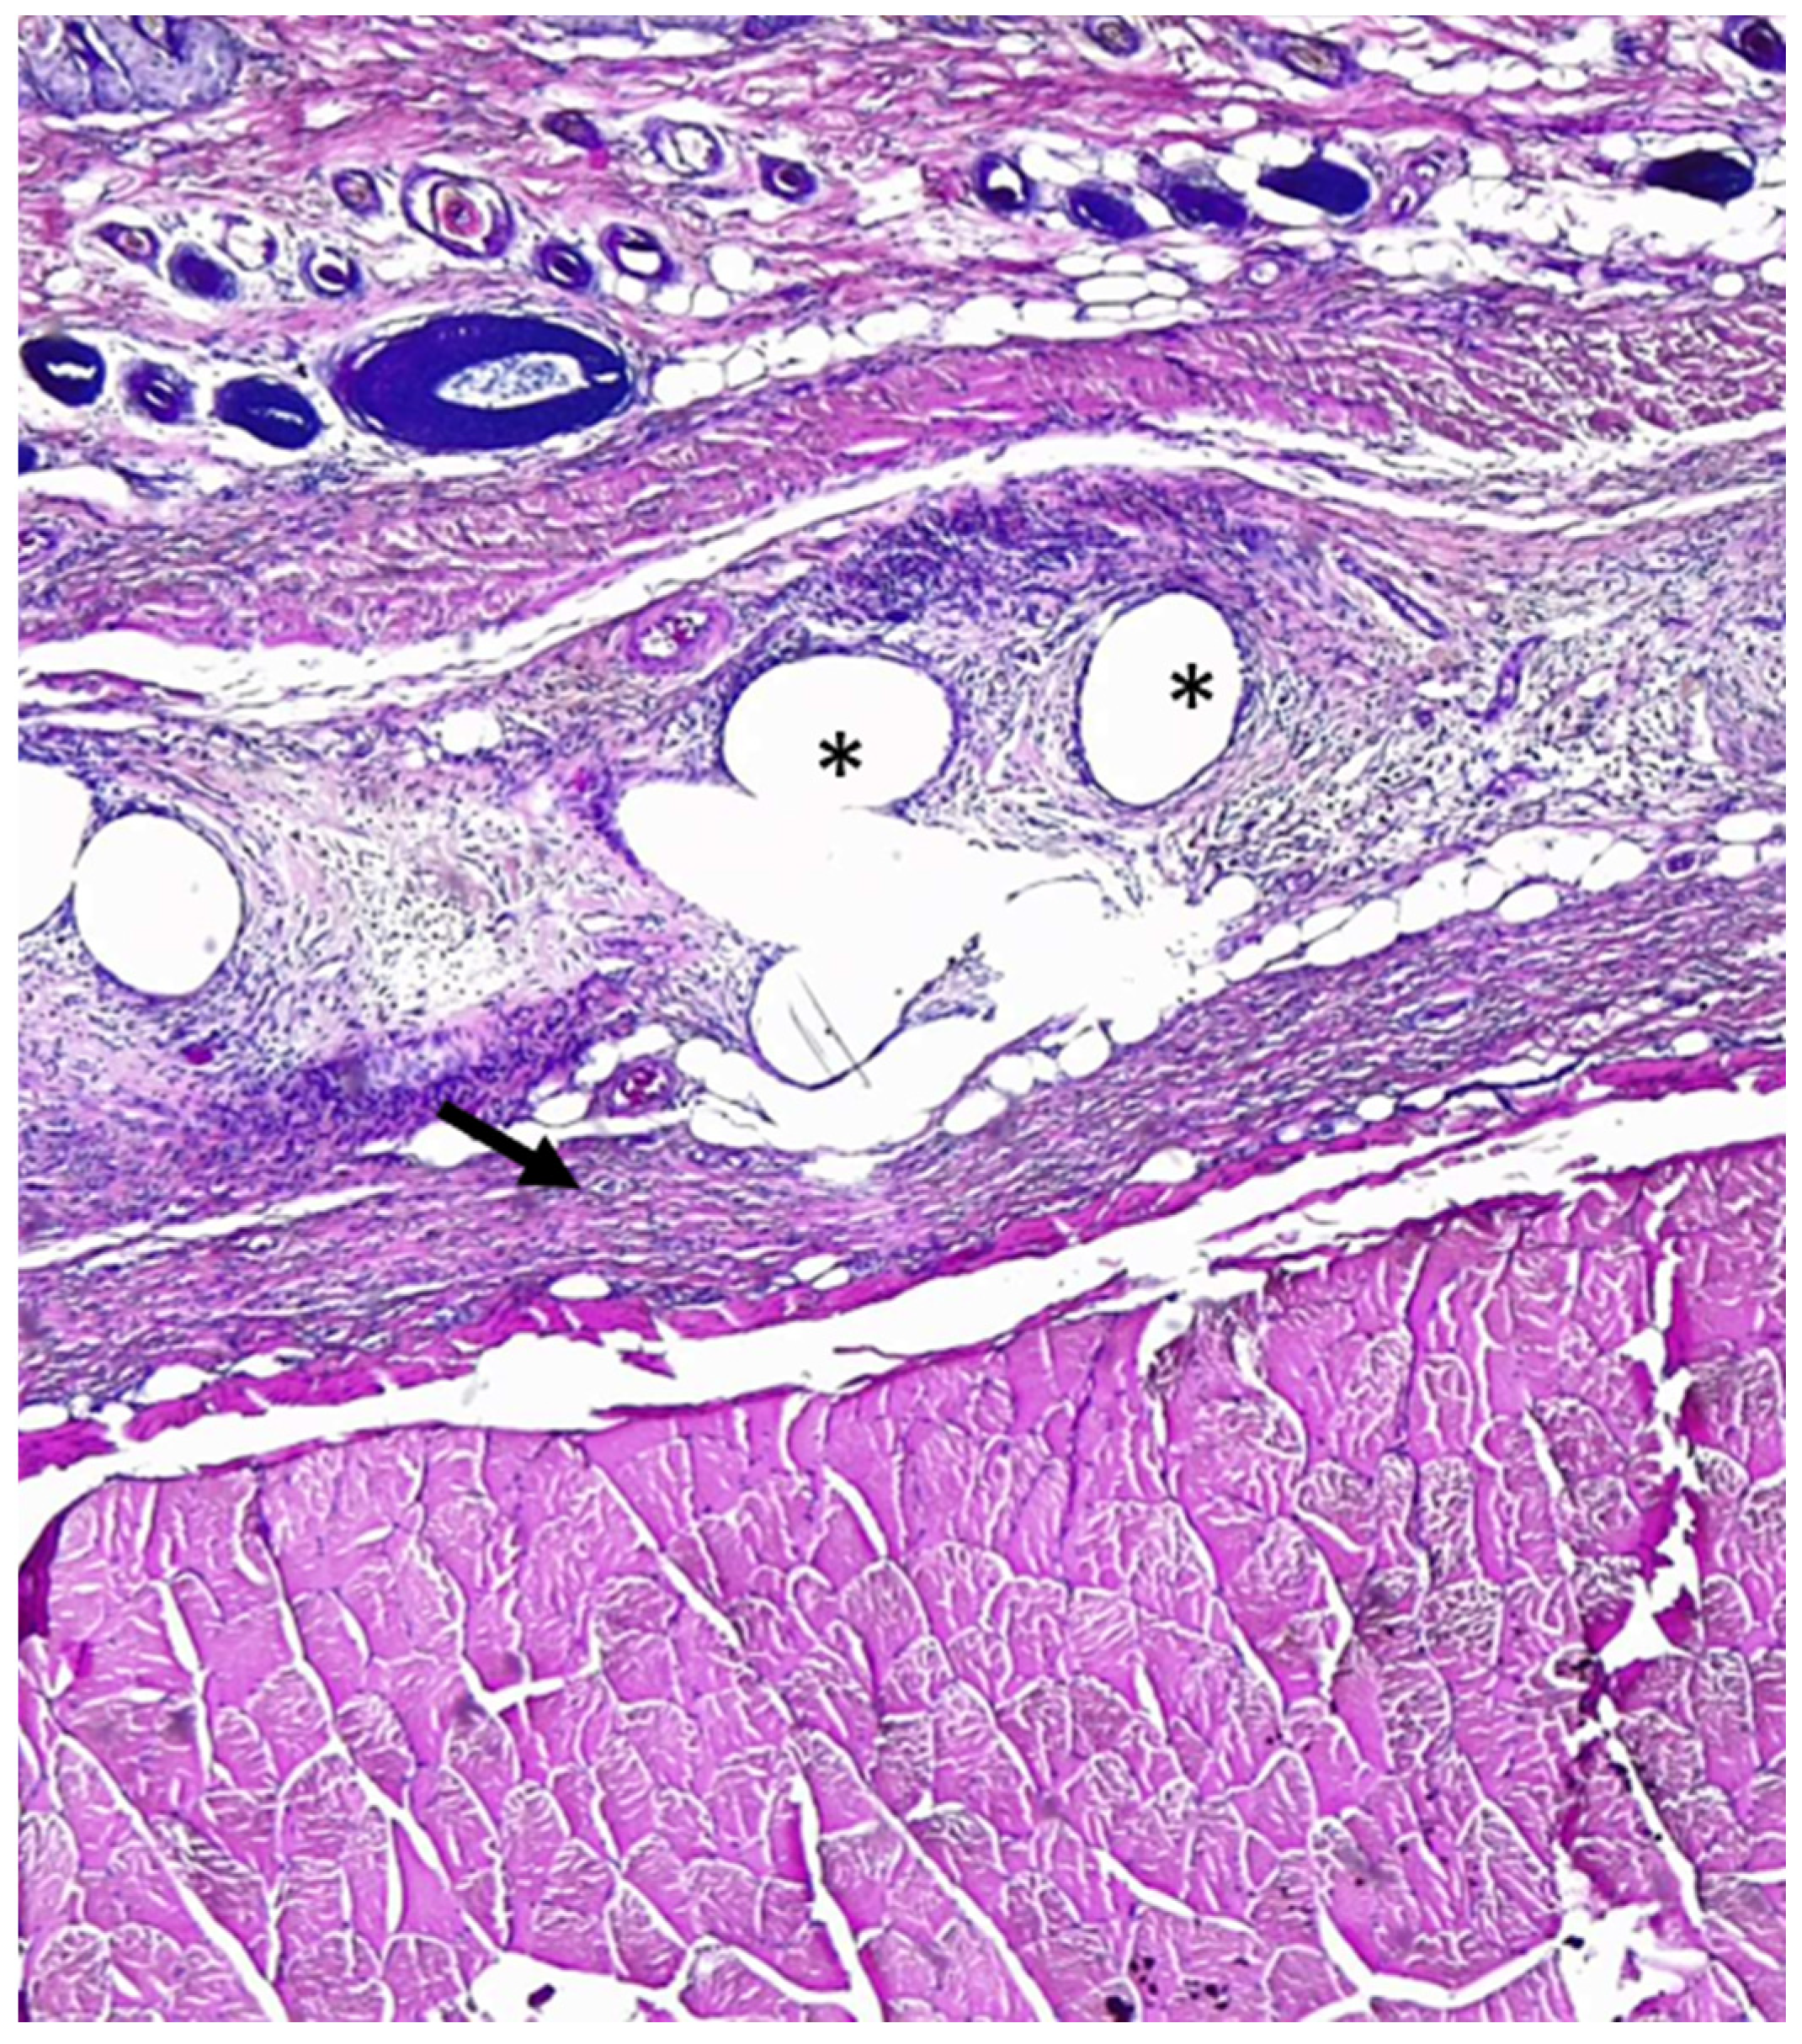

2.3. Histological Evaluation and Immunohistochemical Analysis

5.9. Statistical Analysis